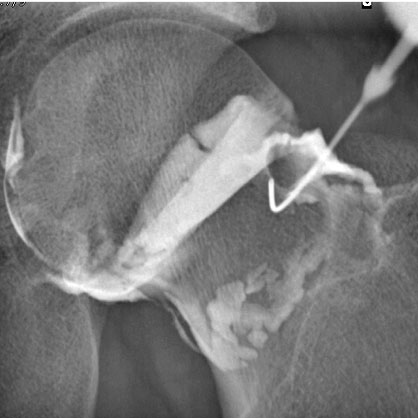

Un grand nombre d'infiltrations s'effectuent sous guidage radioscopique. Pour ces gestes, il est souvent nécessaire d'utiliser un produit de contraste iodé pour vérifier la bonne injection du produit anti-inflammatoire au niveau de la zone souhaitée. Ces infiltrations concernent souvent la colonne vertébrale, mais également les articulations périphériques (épaule, coude, poignet, main, hanche, genou, cheville, pied...).